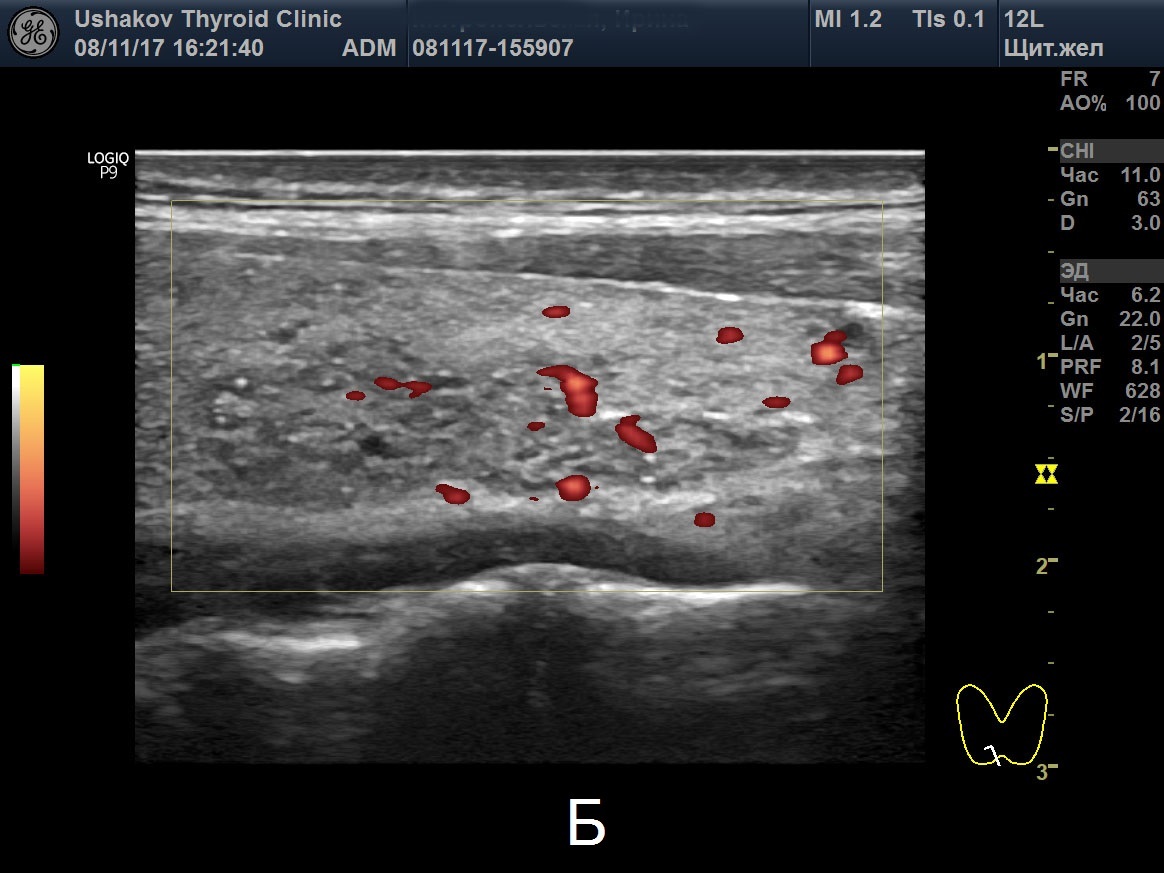

Цдк в узи щитовидной